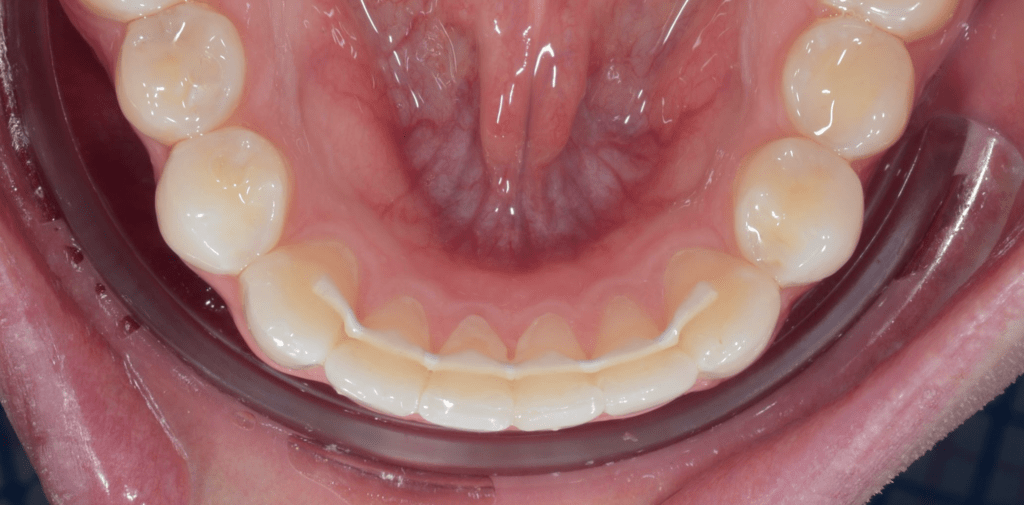

Un fil de contention est un arc fin, discret, collé derrière les incisives et canines. En tant que contention fixe, il agit comme un « retainer » permanent : il neutralise la mémoire élastique des tissus et empêche les dents de reprendre leur place d’origine sur l’arcade dentaire. Concrètement, il bloque les micro-mouvements responsables d’un chevauchement ou de la réouverture d’un diastème – deux complications fréquentes sans rétention.

Comment se pose un fil de contention orthodontique?

La pose d’un fil de contention est une procédure rapide, indolore et parfaitement maîtrisée par les praticiens. Elle se déroule en quelques étapes précises, directement au cabinet, et ne prend généralement pas plus de 15 minutes. Voici comment ça se passe.

*Temps total : ~15 minutes *

- Nettoyage et mise au sec

Le praticien nettoie soigneusement la face intérieure de vos dents, puis place de petits rouleaux de coton (ou une digue) pour garder la zone bien sèche. - Essai du fil

Le fil sur mesure est posé à blanc pour vérifier qu’il s’adapte à l’arcade sans exercer de pression. - Préparation de l’émail

Un gel est appliqué 20 secondes pour créer une micro-accroche, puis la surface est rincée et séchée. - Application de la colle

Une goutte de composite fluide est déposée sur chaque dent qui doit recevoir le fil. - Positionnement et “flash”

Le fil est plaqué contre les dents ; une lampe bleue le fixe en quelques secondes. - Recouvrement

par du composite macrochargé, le fil est recouvert sur chaque dent pour le maintenir en place au long terme - Finition et contrôle

On polit les bords, on vérifie que votre morsure ne touche pas la colle pour s’assurer que tout est lisse et stable.